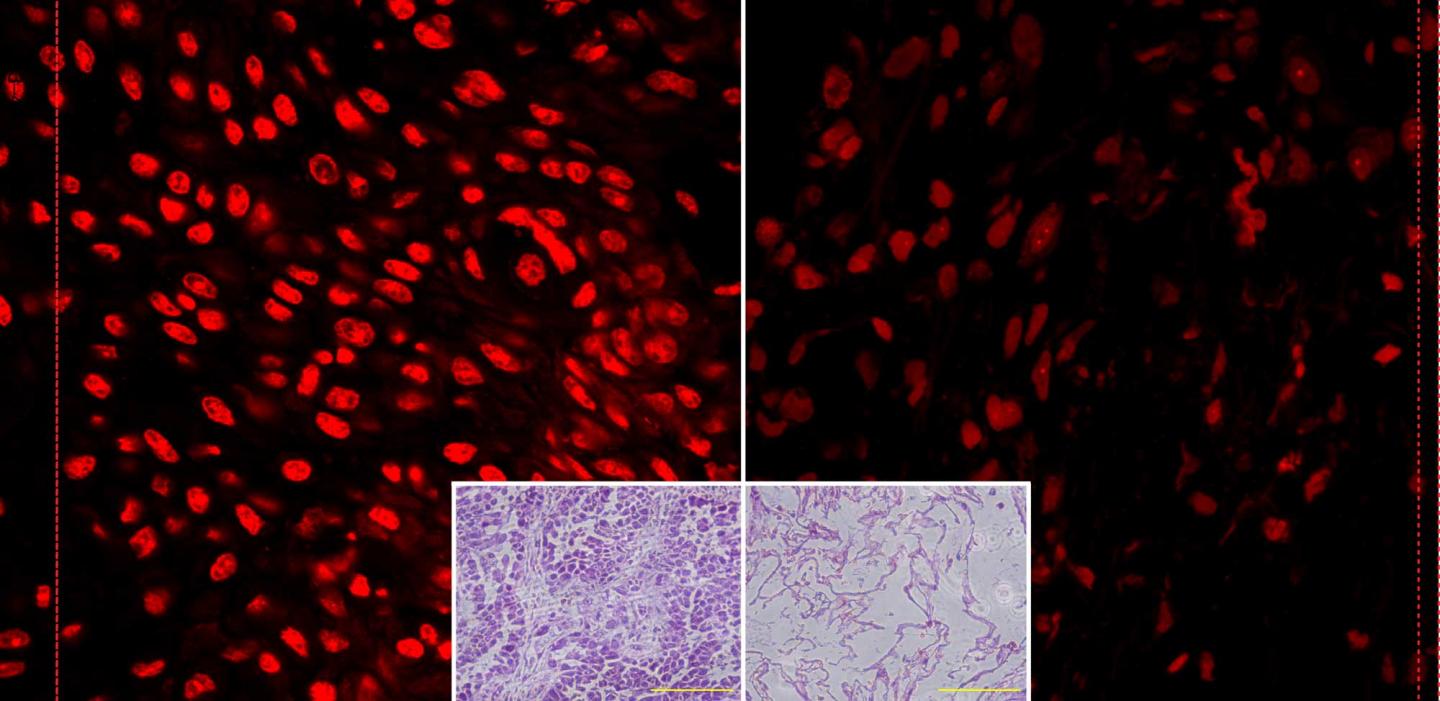

Why is this approach safe? Vitamin C, even at high levels, isn't toxic to normal cells. The research group at Iowa found, however, that tumor tissue's abnormally high levels of redox active iron molecules (a by-product of abnormal mitochondrial metabolism) react with vitamin C to form hydrogen peroxide and free radicals derived from hydrogen peroxide. These free radicals are believed to cause DNA damage selectively in cancer cells (versus normal cells) leading to enhanced cancer cell death as well as sensitization to radiation and chemotherapy in cancer cells.